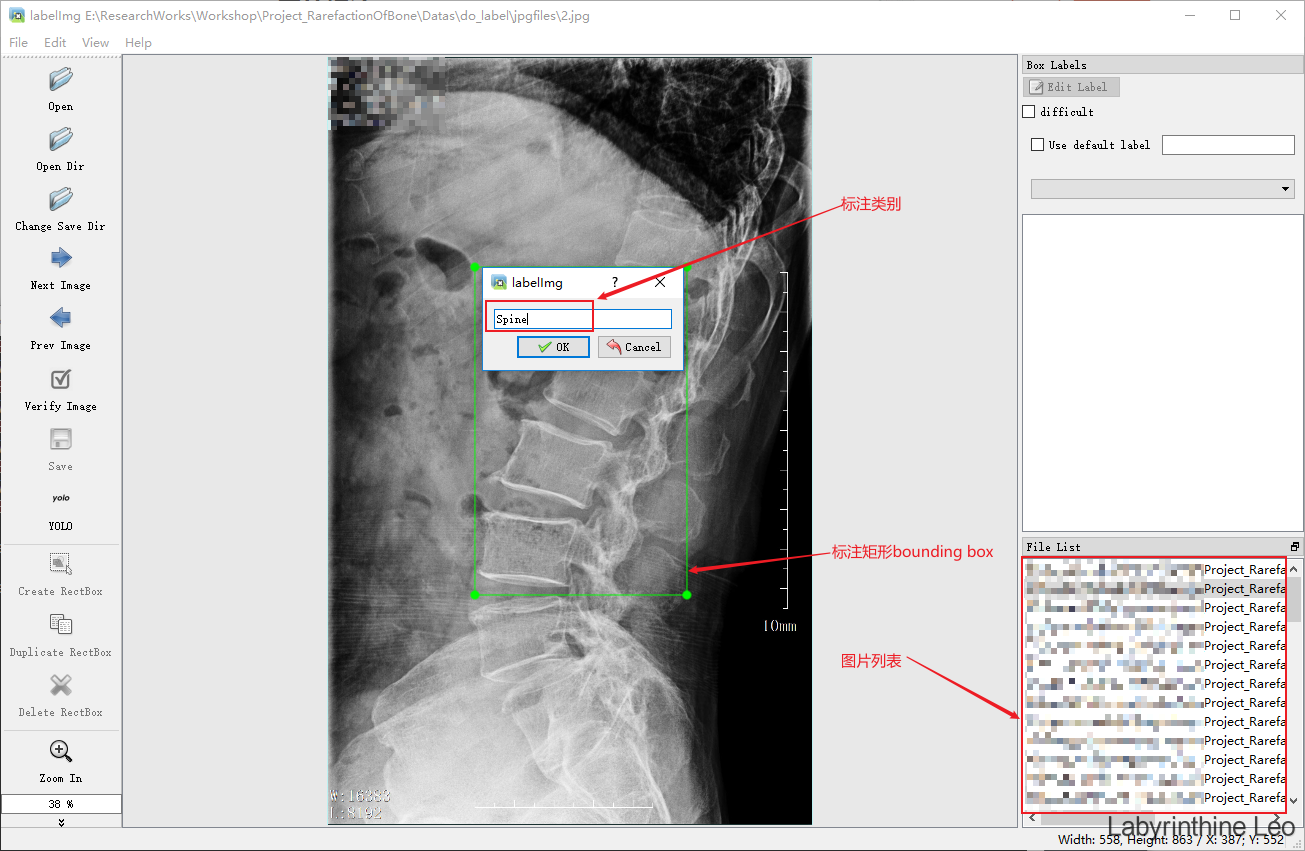

在这里需要特别说明一下关于yolov5图片数据和标签的格式,上文中提到的官网Train Custom Data教程中包含一个步骤Create Labels,就是关于yolov5中标签数据的格式要求。在目标检测中,我们对原始的图片中的目标要进行人工的手动标框,即bounding box,同时设置该目标的类别(类别索引从0开始),如下图所示:

这样这些标框位置、类别等信息都会存为对应的label标签文件,即我们上面所见的/coco128/labels/train2017/*.txt文件,在yolov5中标签信息文件是TXT文件,其中包含了哪些信息,我们来看一下:

如上图所示,每个目标对应的bounding box包含信息:1) bounding box中心x坐标x_center,2) bounding box中心y坐标y_center,3) bounding box的宽width,4) bounding box的高height。需要注意几点:1) 这4个信息均要被归一化为0-1之间的值,2) 这4个信息前加上目标类别class总共5列信息即TXT文件中的标签信息(如下图所示),则构成class x_center y_center width height,3) 类别的索引从0开始。

其实LabelImg的使用很简单,按钮的使用以及图像的标注如下图所示

这里博主自制的图像数据是医疗图像相关的,读者可以以此为鉴自行标注自己的数据。